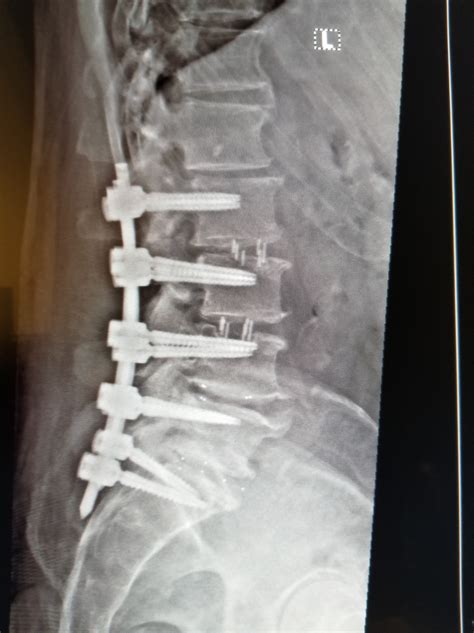

Undergoing back surgery is a significant life event that requires patience, discipline, and a thorough understanding of the healing process. Spinal fusion recovery is a journey that spans several months, as your body works to permanently connect two or more vertebrae to improve stability and alleviate chronic pain. While the prospect of surgery can be daunting, knowing exactly what to expect during the weeks and months following your operation can help you manage your expectations and ensure a safer, more successful outcome. By following medical guidance and adhering to physical therapy protocols, most patients find they can return to a meaningful, pain-free life.

The first few days following your procedure take place primarily in the hospital. Your medical team will focus on pain management and ensuring that you can perform basic movements safely. During this time, you will be encouraged to move around shortly after surgery—usually within 24 hours. Early mobilization is a cornerstone of effective spinal fusion recovery because it reduces the risk of blood clots and helps prevent stiffness.

The Roadmap of Spinal Fusion Recovery

Once you are discharged, the real work begins at home. It is essential to recognize that recovery is not linear; there will be days when you feel significantly better and others where fatigue or discomfort may linger. Understanding the timeline helps you pace yourself appropriately.